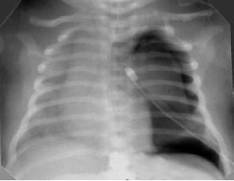

Выраженное снижение пневматизации легких, воздушные бронхограммы, границы сердца практически не различимы, стёрты (Рис.6).

Рисунок 6. РДС. Рентгенограмма грудной клетки в прямой проекции, в горизонтальном положении. Интенсивное мелкоточечное затемнение легочных полей - с-м "матового стекла", на фоне которого не дифференцируется тень средостения. Визуализируются линейные просветления, обусловленные заполненными воздухом бронхами - "воздушная бронхограмма". (Диагностика и лечение РДС недоношенных // метод. рекомендация, 2007)